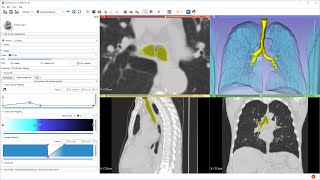

AI assisted segmentation tutorial using 3D SLICER Lung and lobe segmentation with "lungmask" AI in 3D Slicer

Lung and lobe segmentation with "lungmask" AI in 3D Slicer Automatic multi modality AI medical image segmentation in 3D Slicer using MONAIAuto3DSeg extension

AI assisted segmentation tutorial using 3D SLICER Lung and lobe segmentation with "lungmask" AI in 3D Slicer

Lung and lobe segmentation with "lungmask" AI in 3D Slicer Automatic multi modality AI medical image segmentation in 3D Slicer using MONAIAuto3DSeg extension